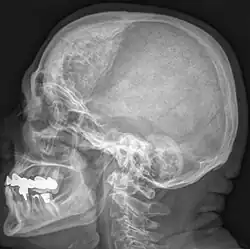

Hyperostosis frontalis interna is a common, benign thickening of the inner side of the frontal bone of the skull. It is found predominantly in women after menopause and is usually asymptomatic. Mostly frequently it is found as an incidental finding discovered during an X-ray or CT scan of the skull.